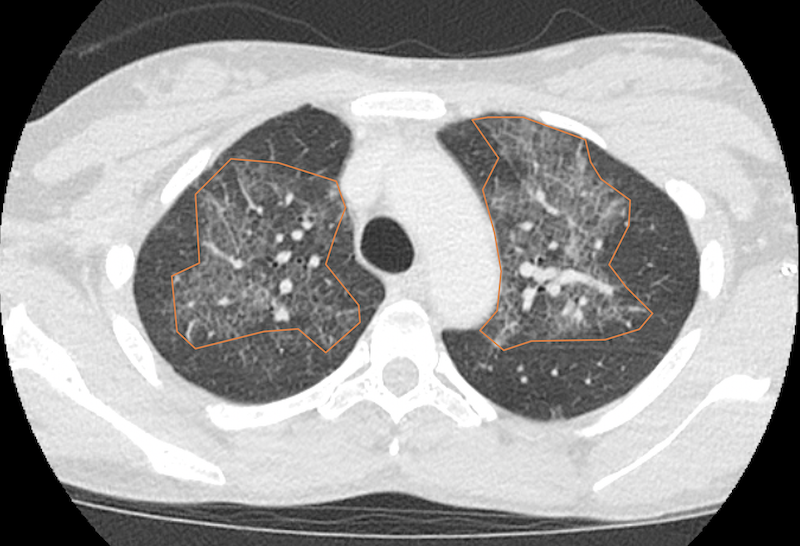

Diagnostic testing. A computed tomography (CT) scan of the chest demonstrated a large right-sided pleural effusion and bilateral airspace opacities (Figures 1 and 2). A thoracentesis was performed. The pleural fluid was milky in consistency and laboratory testing of the fluid showed a high triglyceride content of 474 mg/dL. Radiological findings showed multifocal ground glass opacities and septal thickening (pattern of “crazy paving”) with additional confluent consolidations (Figure 3). Subsequent bronchoalveolar lavage revealed hemosiderin-laden macrophages and atypical lymphocytes, but cultures remained negative, although a respiratory polymerase chain reaction was reactive for Haemophilus influenzae. She also had an elevated b-type naturetic peptide level of 484 pg/mL.

Figure 2b. Non-contrast chest CT scan with lung windows confirming the presence of a large right pleural effusion (orange overlay) with bilateral patchy airspace opacities (solid arrows).

Despite their high lipid content, chylothoraces are highly variable in their CT attenuation due to their high protein content, occasional hemorrhagic components, and lack of detectable fat in CT. Therefore, a thoracentesis should be performed if a diagnosis of chylothorax or pseudochylothorax is suspected.13 The observed "crazy paving" pattern on CT, initially linked with pulmonary alveolar proteinosis, generally represents partial filling of the alveoli. Ground glass opacities and septal thickening are common features.14 In this case, the crazy paving pattern was likely caused by pulmonary edema secondary to sequelae of pre-eclampsia such as capillary permeability and cardiac dysfunction, supported by her elevated B-type natriuretic peptide (BNP) test. With her granulocyte-rich bronchoalveolar lavage, positive H. influenzae test, and other imaging findings, there was likely concomitant atypical pneumonia.15-17